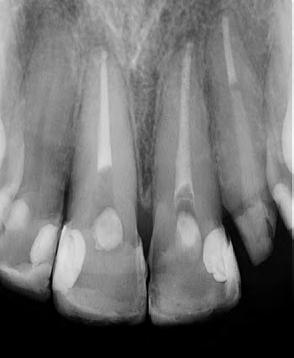

Prof. Dra. Patricia Ferrari

03/2018

Femenino

65 años

Periodontitis Apical Primaria Asintomática. Preparación Químico-Mecánica, Sistemas de limpieza definitiva, Terapia Fotodinámica antimicrobiana (aPDT) y Medicación Intracanal. 12/2018